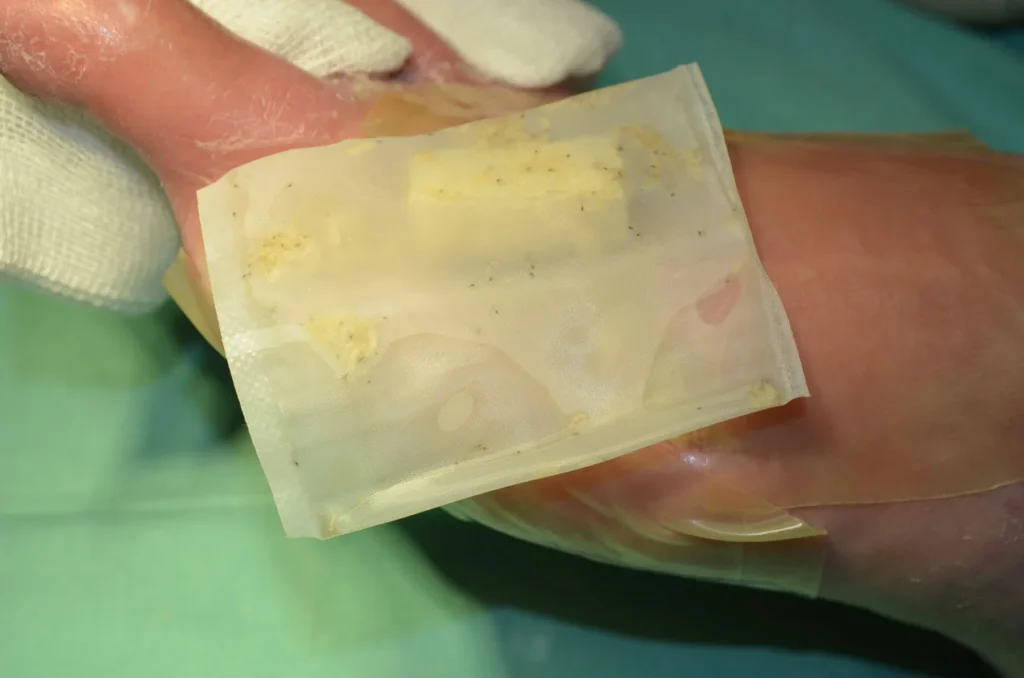

BioBag 50 medizinische Larven

BioBag 100 medizinische Larven

BioBag 200 medizinische Larven

BioBag 300 medizinische Larven

Biochirurgische Therapie mit Fliegenlarven

Zusätzliche – Fotos ![]() 2 Videos

2 Videos ![]() 1

1